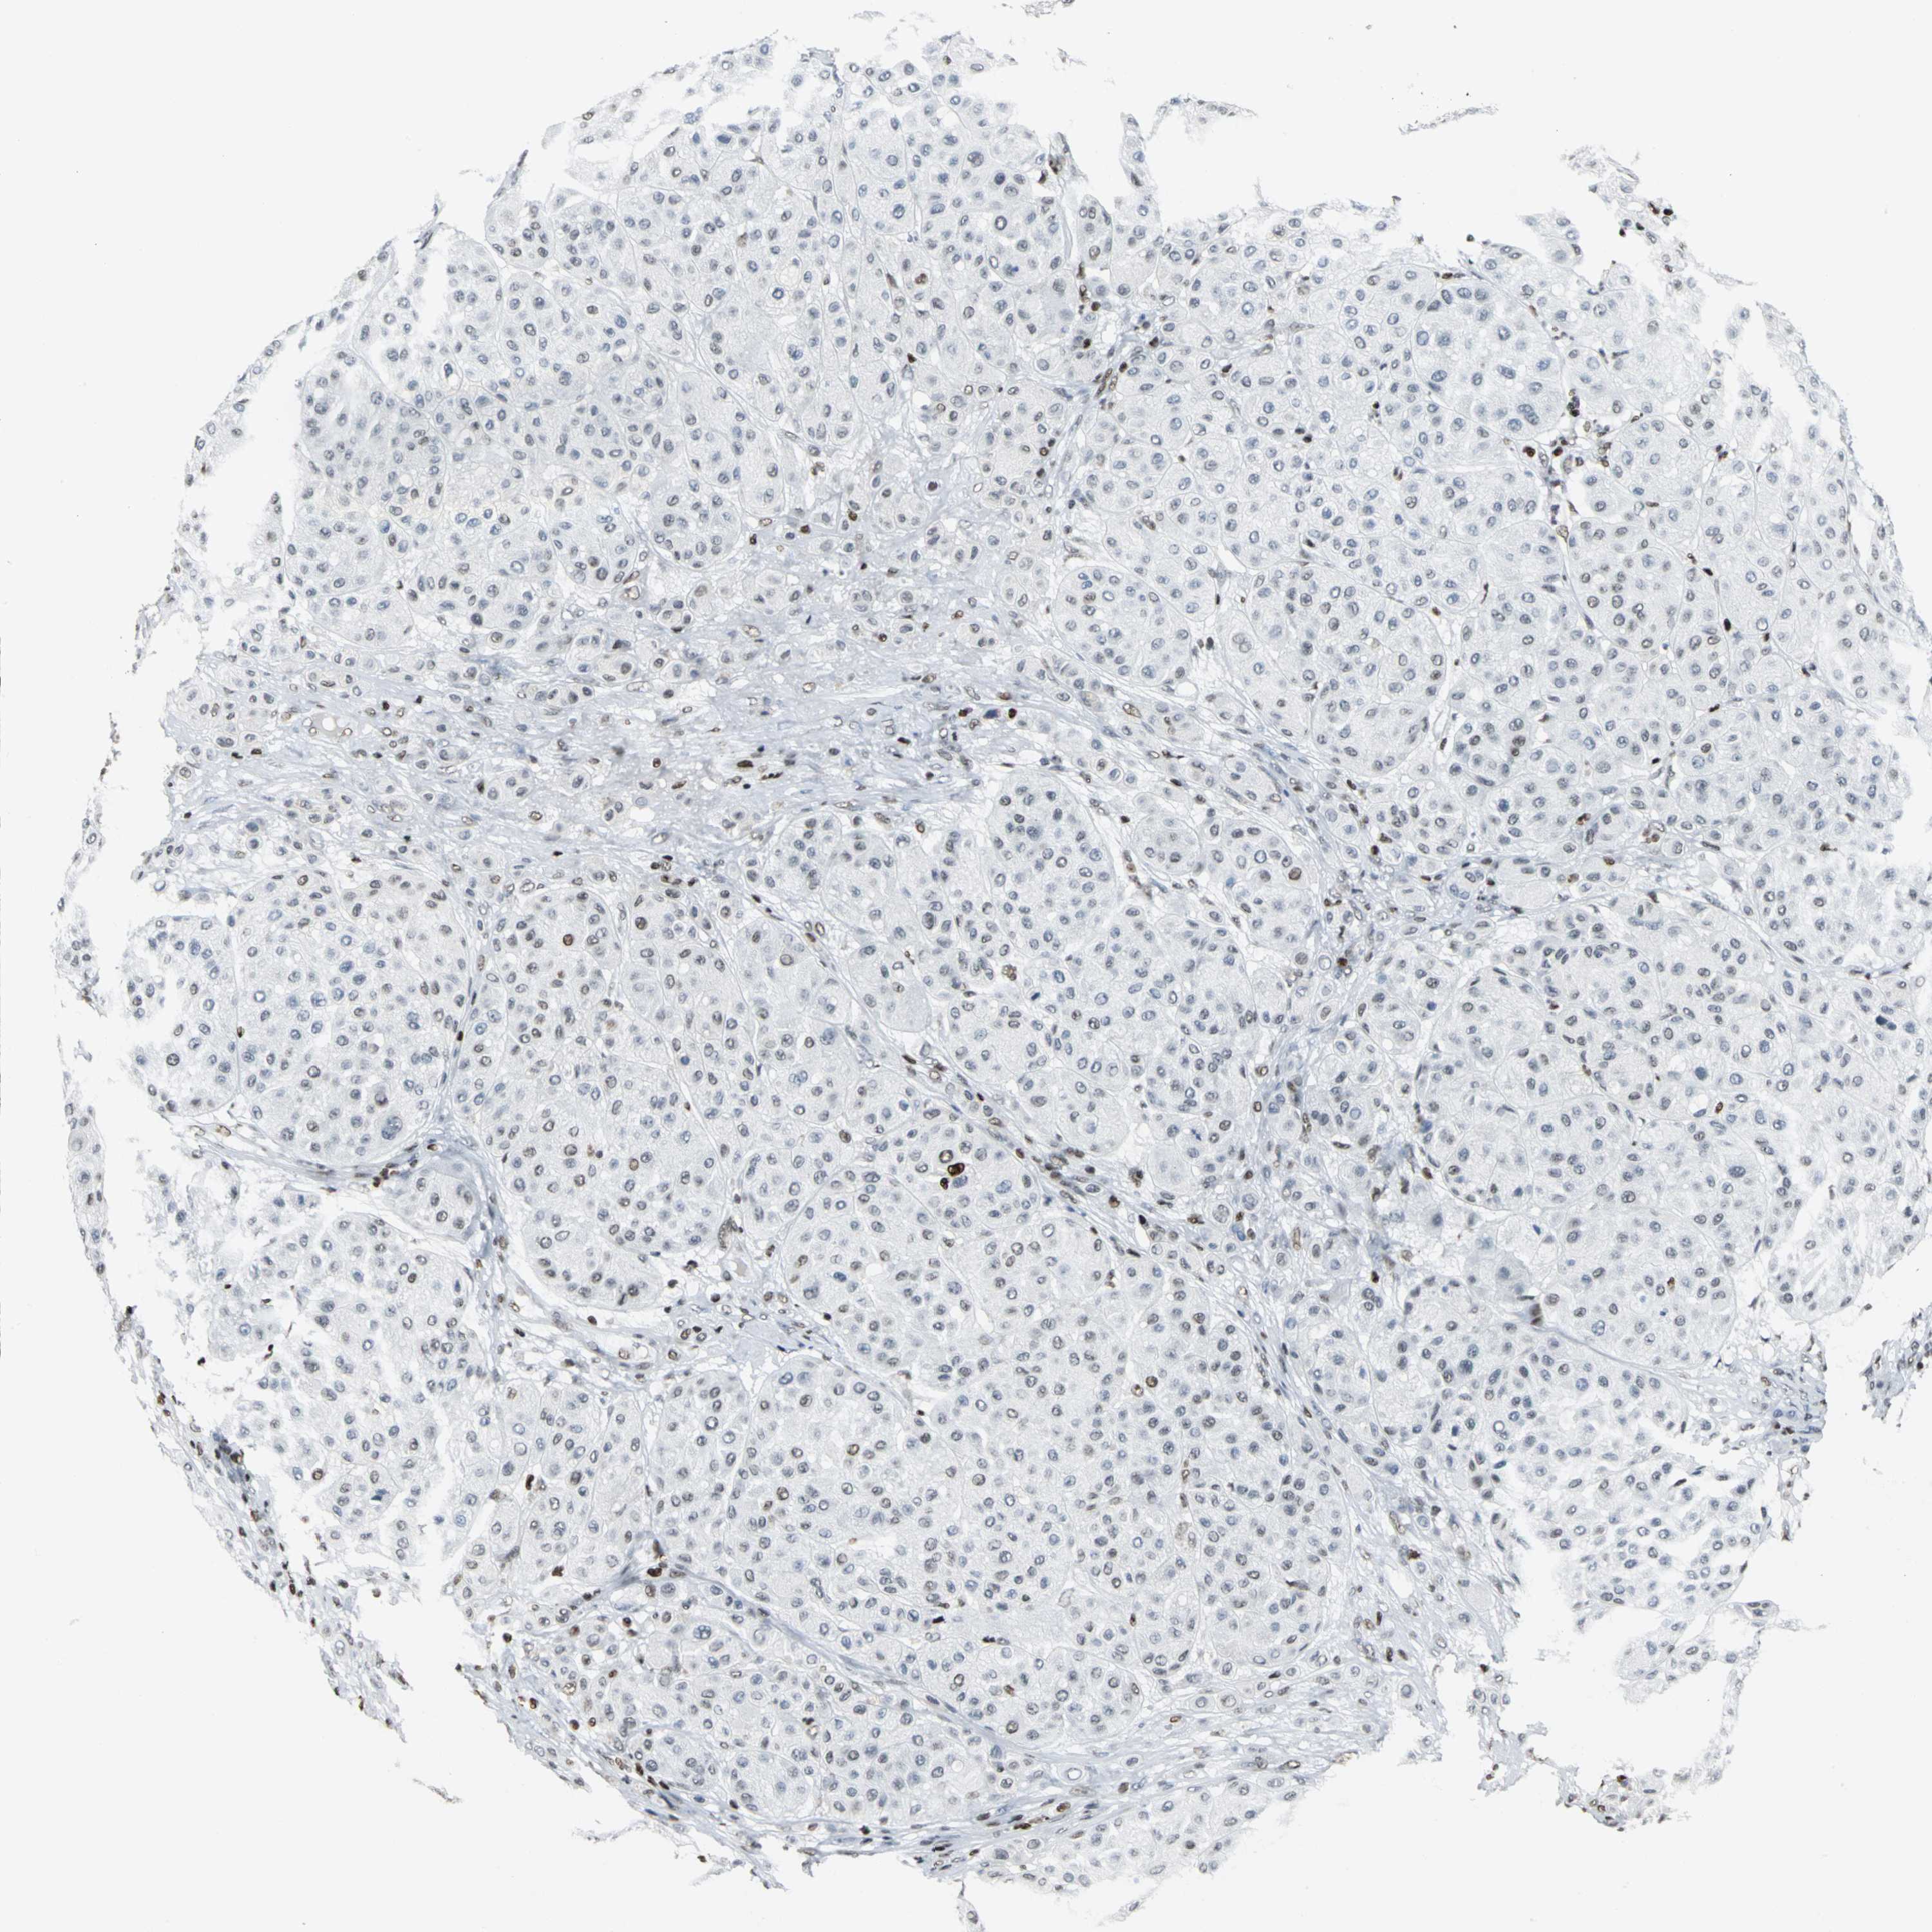

MELANOMA - Protein expressioni

A mouse-over function shows sample information and annotation data. Click on an image to view it in a full screen mode. Samples can be filtered based on level of antibody staining by selecting one or several of the following categories: high, medium, low and not detected. The assay and annotation is described here.

Note that samples used for immunohistochemistry by the Human Protein Atlas do not correspond to samples in the TCGA dataset.

Antibody stainingi

Antibody staining in the annotated cell types in the current human tissue is reported as not detected, low, medium, or high, based on conventional immunohistochemistry profiling in selected tissues. This score is based on the combination of the staining intensity and fraction of stained cells.

Each image is clickable and will lead to virtual microscopy that enables deeper exploration of all samples and also displays staining intensity scores, fraction scores and subcellular localization as well as patient and tissue information for each sample.

Antibody HPA004911

Staining

High

Medium

Low

Not detected

Intensity

Strong

Moderate

Weak

Negative

Quantity

>75%

75%-25%

<25%

None

Location

Nuclear

Cytoplasmic/membranous

Cytoplasmic/membranous,nuclear

Malignant melanoma, NOS

Malignant melanoma, Metastatic site